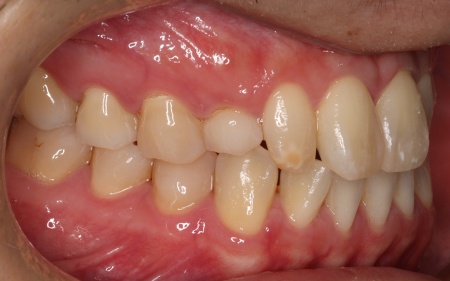

30代男性 歯が欠損した部分を片側固定ブリッジで補った症例

②失った歯の手前の前歯1本を支えとして、2本分の被せ物を装着する片側固定ブリッジ

メリット:外科的な処置を行わずに歯を補える。一般的なブリッジでは前後の歯を削る必要があるものの、今回は手前の歯のみを土台とするため、削る歯の本数を最小限に抑えられる

それぞれのメリット・デメリットをご説明したところ、患者様は当初①のインプラント治療をご希望でしたが、矯正治療の併用や治療期間の長さへの不安から、最終的に②の片側固定ブリッジを選択されました。

また今回はブリッジを装着するためのスペースがやや不足しているため、手前の歯を小さめに削って必要なスペースを確保する必要があることも併せて説明しています。

被せ物の素材は患者様と相談のうえ、自然な白さがあり変色や劣化が起こりにくいセラミックを選択しました。

まず手前の歯を削って土台を作り、精密な型取りを行います。

後日、完成したブリッジを装着し、噛み合わせなどに問題がないかを確認して治療を終了しました。